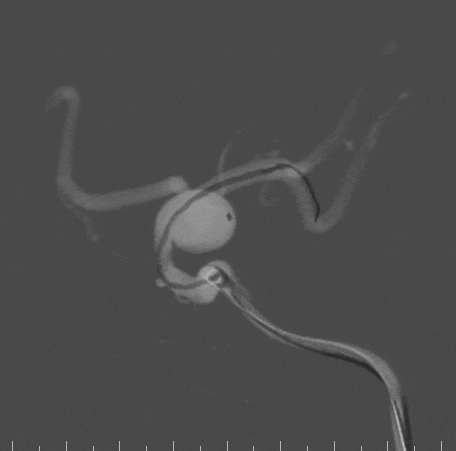

XT-27支架导管及Echelon-10栓塞导管到位后,经支架导管引入4.0*25mm YonFlow®血流导向密网支架,跨瘤颈逐渐打开支架。

完全释放YonFlow®血流导向密网支架,确认支架位置满意,经微导管填入两枚弹簧圈,然后解锁支架近端,支架导管跟进顺利,支架打开良好。

术后即刻可见支架内血流通畅,动脉瘤内可见明显造影剂滞留,远端分支显影无缺失。

术后Vaso-CT示支架贴壁良好,Xper-CT未见出血。